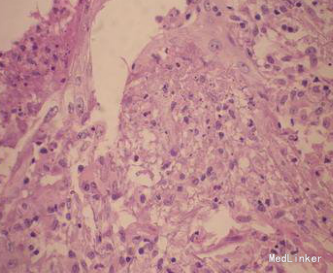

皮肤科检查:四肢、躯干散在分布红色丘疹、结节,米粒至花生米大。部分中央破溃、结痂,部分有轻微疼痛。四肢伸侧可见淡褐色瘢痕。实验室检查:血尿常规正常,胸部x线正侧位未见异常;结核菌素试验强阳性。右上肢皮损组织病理检查:表皮稍增生,真皮炎症浸润呈楔形,真皮浅中层血管周围见淋巴细胞、组织细胞为主的炎细胞浸润。

诊断:丘疹坏死性结核疹。治疗:链霉素肌肉注射,每日1次,利福平早上空腹顿服,雷米封3次/d。随访3个月后皮损全部消退,未见新出皮损,目前随访中。